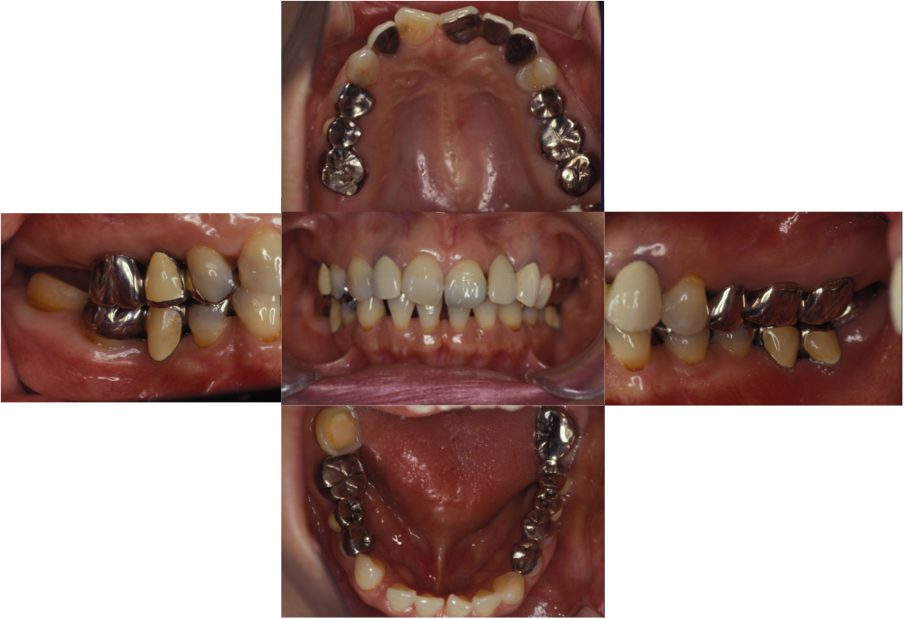

| 主訴 | 全顎治療希望、右下の歯が動いて痛いので噛みずらい。当院でインプラント治療したお母様からの紹介 |

| 治療内容 | プラークコントロール不良なため歯周治療を行い、保存不能の歯を抜歯し、抜歯窩の治癒を待って、欠損部にインプラントを施し咬合再構成を行う。 プロビジョナルレストレーションによる咬合関係を模索した後、全顎にわたりセラミックによる補綴治療、その後メインテナンスに移行 |

| 治療費 | 3,020,000円(税込)(インプラントすべて含む) |

| 治療期間 | 8ヶ月 |

| 治療回数 | 48回 |

| 想定されたリスク | 食いしばり(パラファンクション)によるセラミックの破折、歯の破折 |